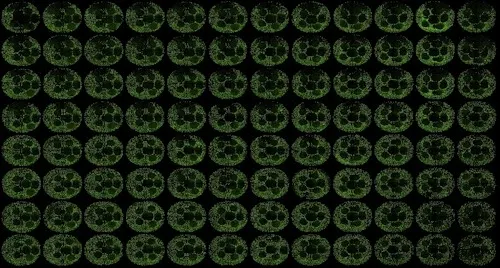

肝臓オルガノイドは、前臨床段階で薬剤性肝障害をおよそ80%の精度で予測します。オルガノイドを用いた薬剤性肝障害の予測は、薬剤の安全性を向上させ、新しい治療法の発見を加速し、薬剤障害の主な原因をより迅速に特定することができます。ダナハー、モレキュラーデバイス、シンシナティ小児科の幹細胞・オルガノイド医学センター(CuSTOM)の協力により、肝臓オルガノイドのスケールアップ生産を可能にするハイスループット技術が実現します。これには、細胞バンクを構築し、ヒトの遺伝子をよりよく反映させ、臨床試験における多様性を向上させる構想も含まれています。

オルガノイド科学を発展させるために私たちが抱いている中核的な信念は、オルガノイドの生成から当て推量を取り除くことです。CellXpress.aiプラットフォームのような自動化技術の設計は、その信念を支えるものです。例えるなら、このテクノロジーは、細胞を入れるとオルガノイドが出てくるオーブンのようなものです。オーブンに例えるなら、すぐに使えるケーキミックスが理想的なアプローチです。このエンドツーエンドを達成するために、私たちは、スクリーニング・ツールとして使用するためにスケールアップする際に再現性と一貫性を確保できるよう、標準的な方法と品質管理を浸透させることによって、次のレベルに引き上げることに注力してきました。

ここで、シンシナティ小児病院医学センターの幹細胞・オルガノイド医学センター(CuSTOM)が登場します。このグループがパートナーとしてユニークなのは、小児患者や肝移植患者など、必要とする人々にオルガノイドを提供するためのオルガノイド医療を実現するという、臨床的使命に駆り立てられた幹細胞研究機関としての立場です。患者の治療というエンドポイントに到達するためには、スクリーニングにオルガノイドを採用する際に関連するすべての問題-スケール、スループット、再現性、一貫性-が関係してきます。CuSTOMのユニークな点は、イノベーターが新しい方法を開拓し、成功したプロトコルに到達した後は、信頼性の高いオルガノイド開発ワークフローの合理化と最適化にかなりの時間を費やしている点です。メソッドをより効率的でスケーラブルなものにするために労力を費やすことに、ファンファーレや学術的栄光はあまりありません。しかし、このような作業は、臨床オルガノイド・パイプラインを構築するというCCHMCの使命に直結します。

方法、培地、プロトコルを微調整するために、かなりの量の作業を前もって行う必要があります。これは、何かが革新的なモデルから主力技術へと進歩するための基本的な側面です。例えば、ある患者のセルに特異性レベルで作用するように最適化された方法が、別の患者に合うように条件を調整する必要がないとは限りません。スケーラビリティの問題に対処するために必要なのは、大規模な患者サンプル集団で機能する適切な方法と条件を見つけることです。これがCuSTOMが完成させる作業です。完成後は、細胞が穏やかに扱われ、ストレスを受けず、自発的に分化していることなどを確認するために、結果を検証する必要があります。モレキュラーデバイスは、当社のCellXpress.aiプラットフォームと専門知識を活用して支援します。